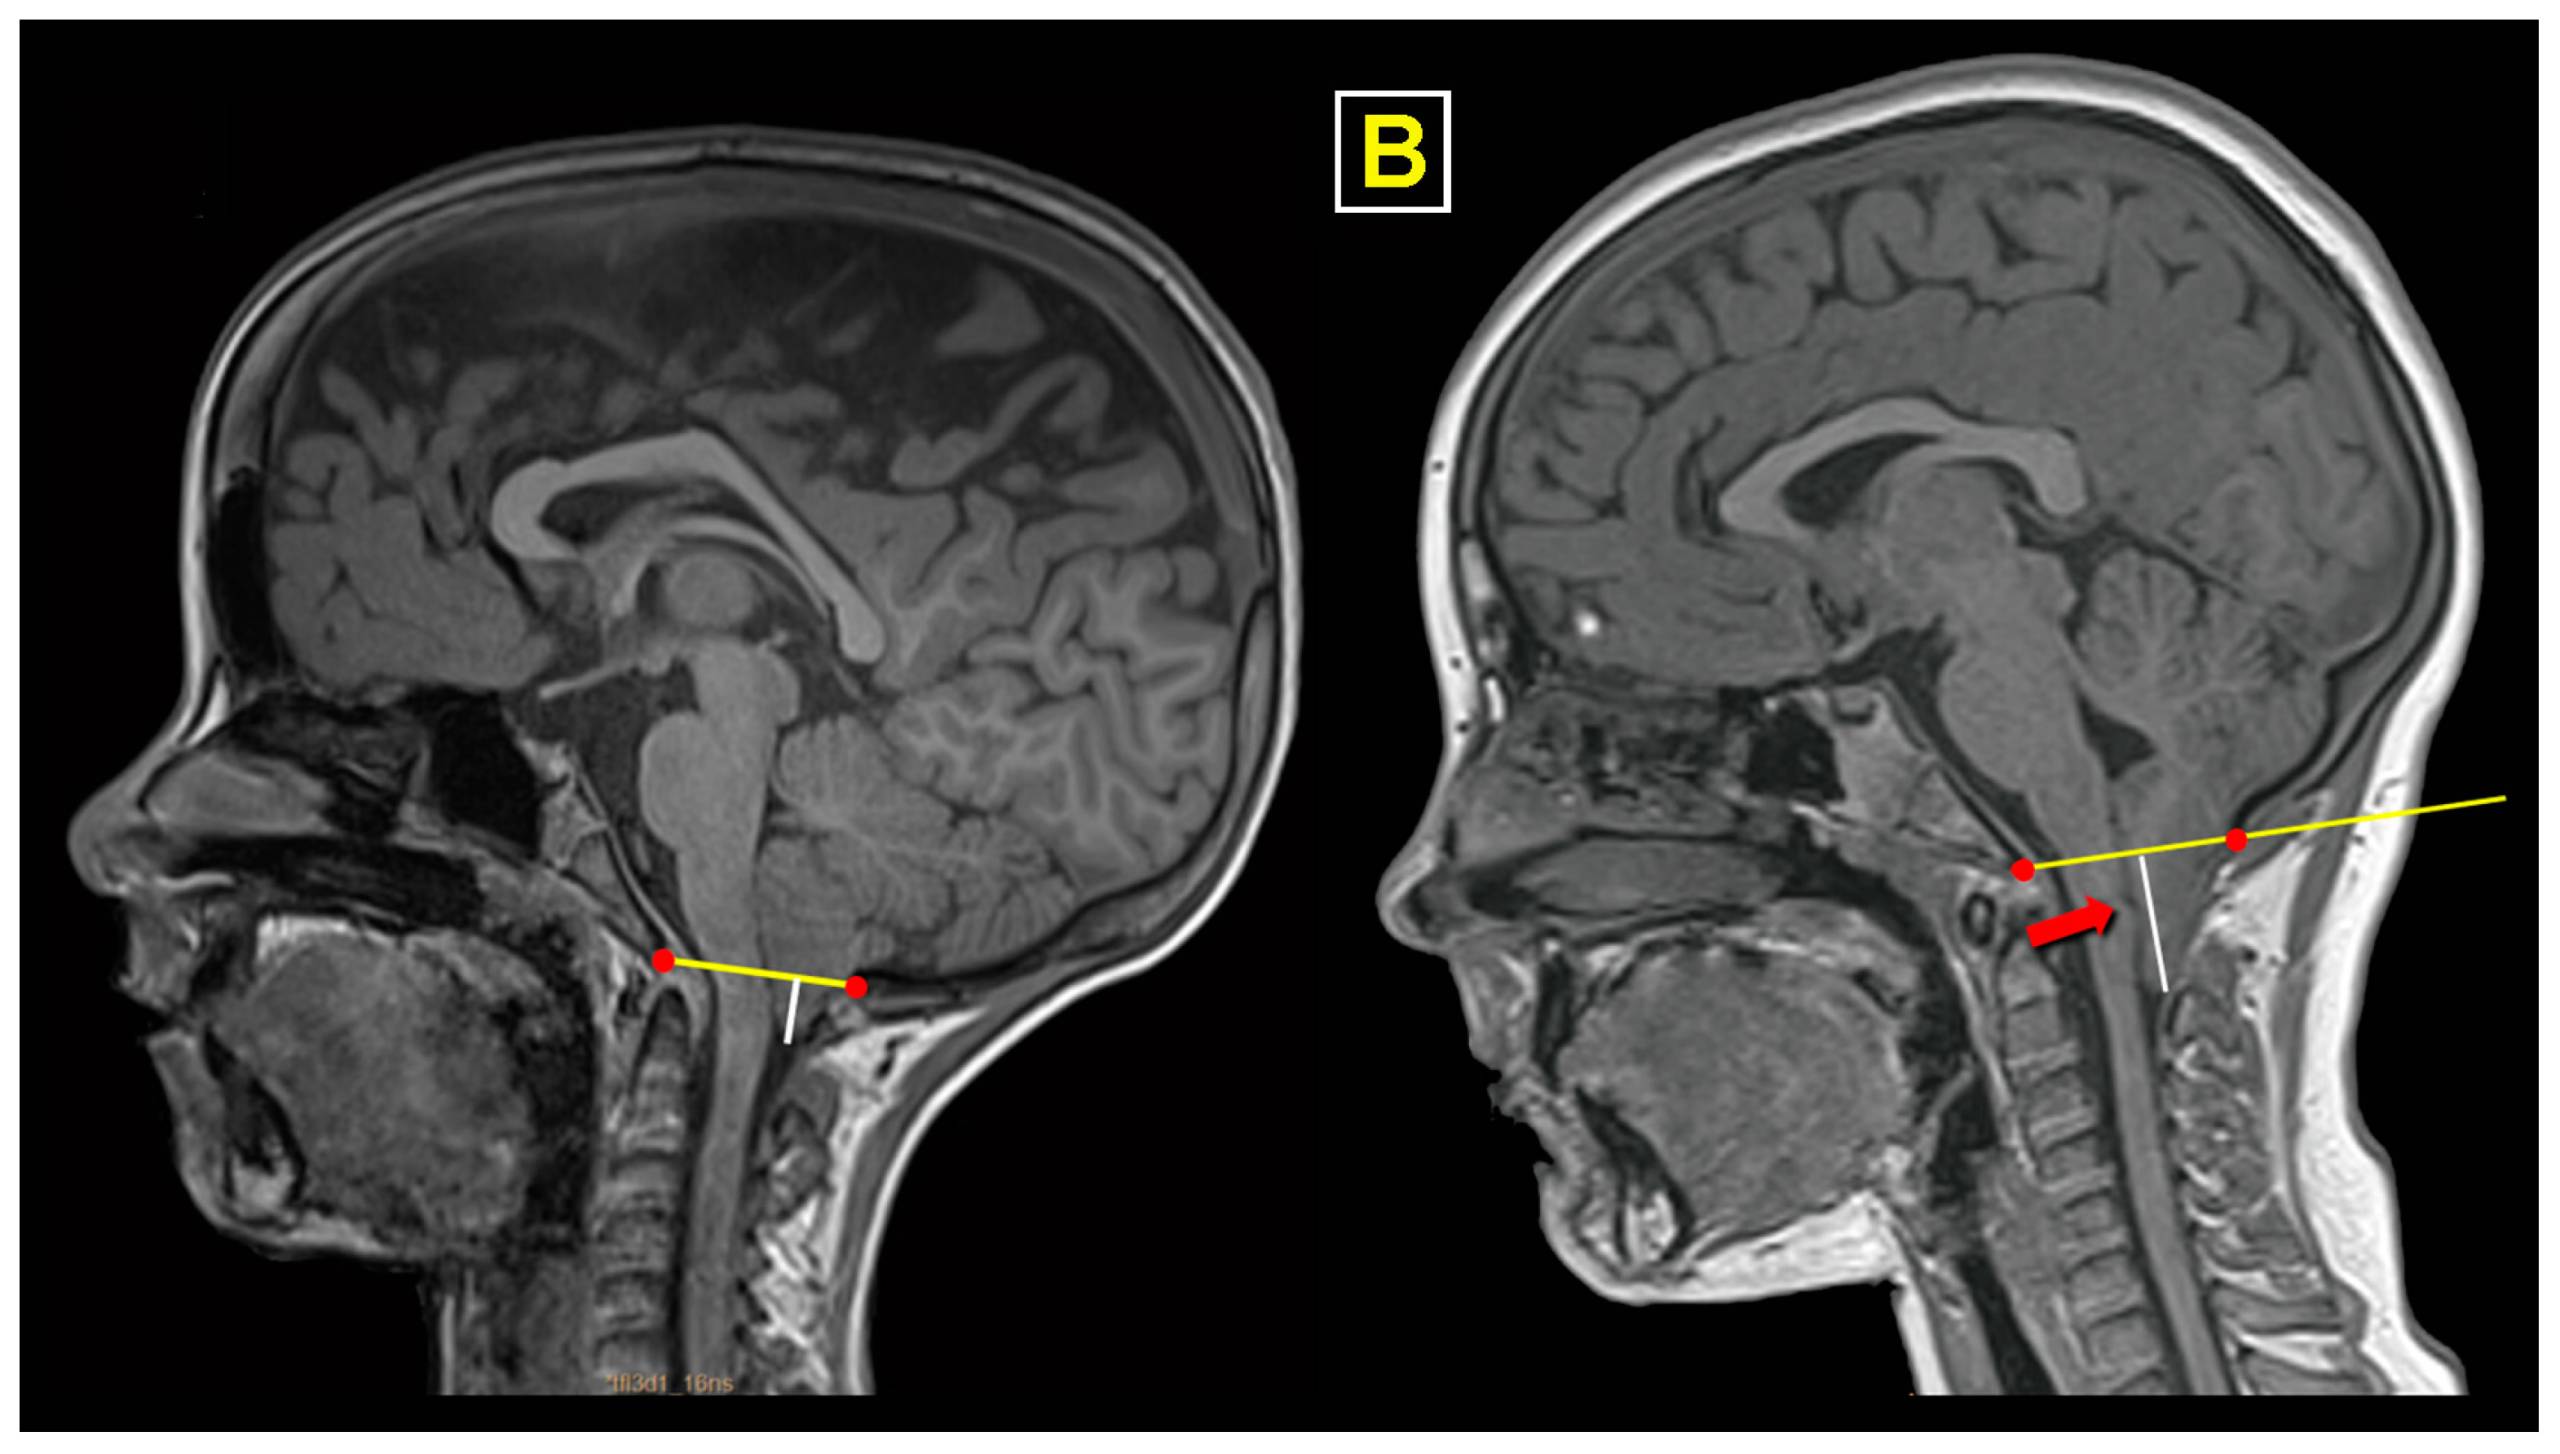

Magnetic Resonance Imaging (MRI) is the primary diagnostic tool for Arnold–Chiari malformation. The evaluation process includes:

- MRI of the brain and cervical spine

- Assessment of cerebrospinal fluid flow

The goal is to assess not only the anatomical displacement but also its functional consequences